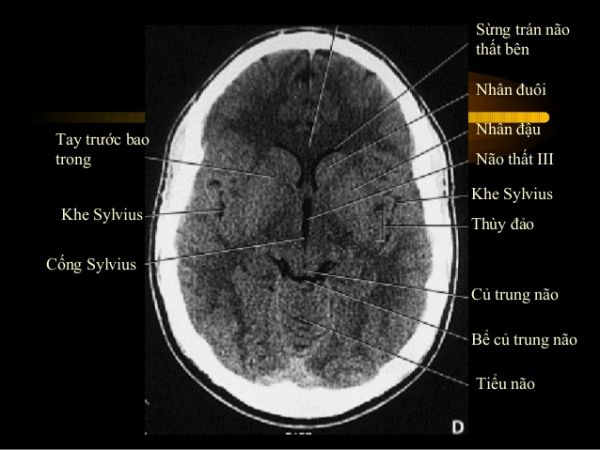

Nhồi máu tiểu não